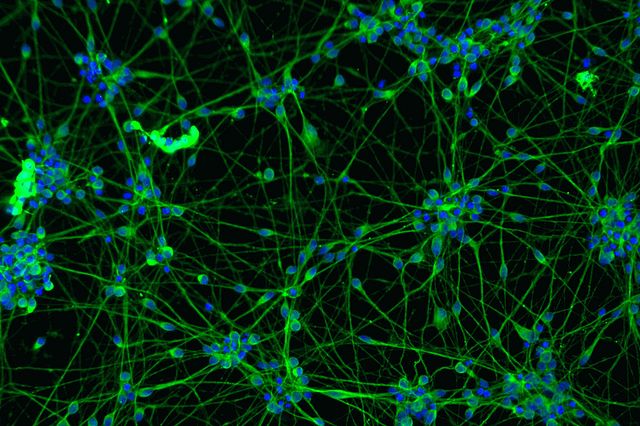

Иллюстрации из Cell Discovery: Удивительный мир науки через фотографии

Раздел: Фотоэссе